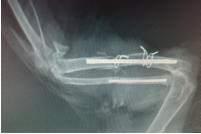

Die Röntgenstrahlen durchdringen den Körper und ermöglichen so innerhalb weniger Minuten ein Bild von den Knochen und den inneren Organen unserer Haustiere zu bekommen. Das Röntgenbild leistet unter anderem bei Lahmheiten und der Diagnose von Krankheiten des Herzens, der Verdauungsorgane und der Harnwege wertvolle Dienste. In der Ordination steht ein modernes Röntgengerät mit digitaler Entwicklung zur Verfügung, Vorteile sind die hervorragende Bildqualität für genaue Diagnostik, Versand der Bilder per e-mail (an den Besitzer) und Archivierung am Computer.